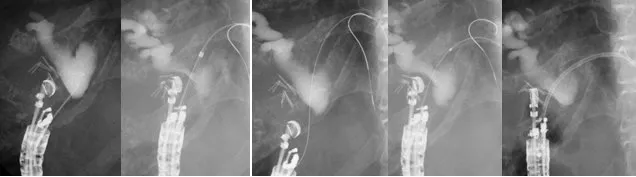

超音波内視鏡下胆管ドレナージ術(EUS-CDS)【下図】

黄疸を発症したが膵頭部癌による十二指腸狭窄のため、経乳頭的胆管ステント留置術が困難と判断されて紹介された。十二指腸球部よりEUS-FNAを用いて胆管を穿刺し、胆管ステント留置術を行った。十二指腸狭窄部に対しては、内視鏡的十二指腸ステント留置術を行い、再び食事摂取が可能となった。 - 超音波内視鏡下胆のうドレナージ術(EUS-GBS)